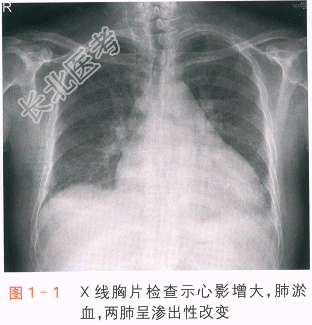

血常规检查:RBC4.22×10¹²/L,PLT215×10⁹/L,WBC6.24×10⁹/L,N70.5%。INR1.77。TB46.9μmol/L,DB26.5μmol/L,A/G35/55(g/L),ALT/AST167/77(IU/L),Na⁺/K⁺/Cl⁻129/4.5/90(mmol/L),BUN21.2mmol/L,Cr/UA169/394(μmol/L),CK/CK-MB52/12(IU/L),TC/TG4.11/1.05(mmol/L),HDL-C/LDL-C0.32/3.31(mmol/L)。心肌肌钙蛋白T(cTnT)0.080ng/ml,氨基末端脑钠肽前体(NT-proBNP)11790.0pg/ml。甲状腺功能正常。X线胸片检查:心影增大、肺淤血、两肺渗出性改变(见图1-1)。超声心动图检查:左心房左心室明显扩大变薄伴整体收缩活动减弱,LVEF33%,二尖瓣中度反流,右心房扩大,中度肺动脉高压。心电图检查:房颤,频发室早,QRS波时限为106ms(见图1-2)。B超检查提示肝淤血肿大,双肾缩小,少量腹腔积液。